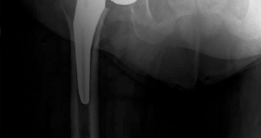

Clinical & Radiographic Imaging